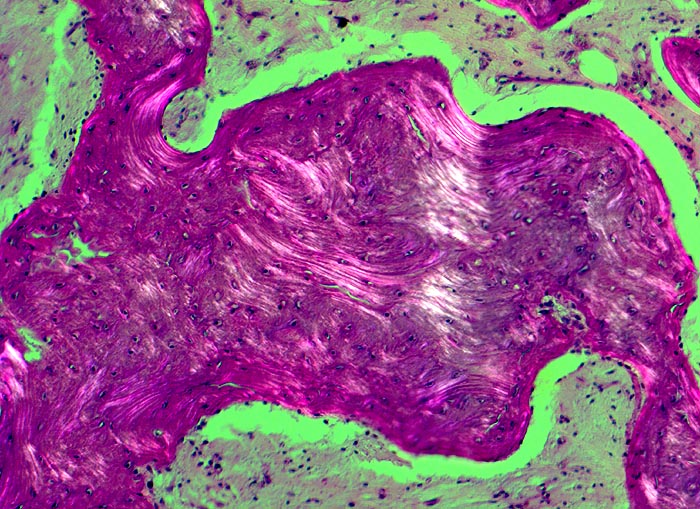

• Die Spongiosabälkchen sind auffallend verdickt, vermehrt und unregelmässig geformt.

• Prominente Zementlinien sind mosaikartig angeordnet.

• Lockere Markfibrose.